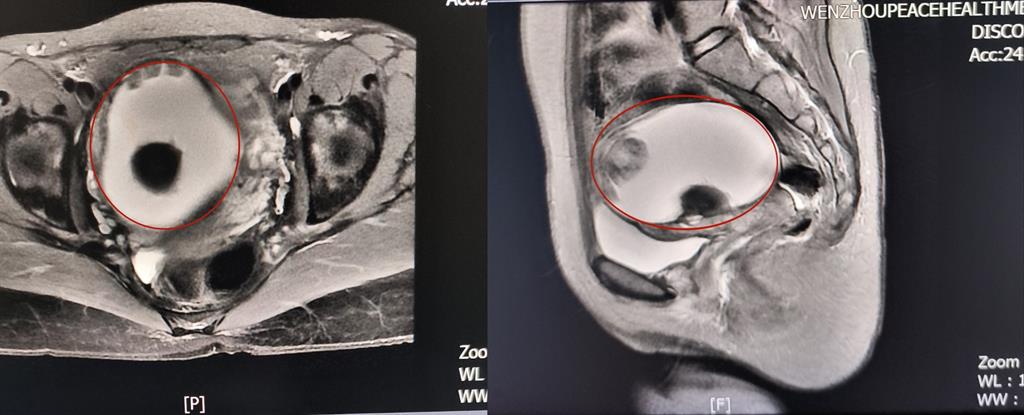

前不久,溫州某高校外籍教師A女士來到和平國際醫(yī)院體檢與健康管理中心進行深度體檢。B超提示“子宮右側(cè)附件區(qū)囊性塊,大小約82*79*88mm”和平國際醫(yī)院婦科主任醫(yī)師方軼萍發(fā)現(xiàn),A女士還有三項腫瘤標志物數(shù)據(jù)超標(甚至高出正常值兩倍)。

卵巢腫瘤?為進一步明確診斷,A女士在方主任建議下做了增強磁共振,影像結(jié)果提示:盆腔右側(cè)團塊狀占位伴多發(fā)成熟脂肪成分大小約89*100*71mm,考慮畸胎瘤可能性大。謎團逐漸解開,原來那個“怪胎”可能是畸胎瘤在作祟。